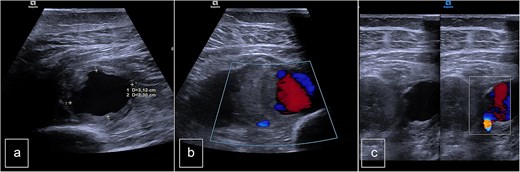

The patient was a 55-year-old female who was admitted to the Surgery Department due to recurrent bleeding and swelling at the surgical site following the removal of elective osteosynthesis material from the left tibia and patella by orthopedic surgeons. Initial investigation involved Doppler ultrasonography of the left leg, which revealed a large hematoma within the deep muscle structures of the proximal and middle thirds of the calf. An anechogenic pocket, exhibiting arterial flow on Doppler-color imaging, was identified, consistent with a pseudoaneurysm with dimensions of 28 × 20 × 24 mm, and it was supplied by arterial flow from the posterior tibial artery (PTA). The PTA remained patent distally but demonstrated a demodulated, monophasic flow with a velocity of 12 cm/s (Fig. 1).

Preoperative duplex sonography. (a) M-mode. Pseudoaneurysm of the posterior tibial artery (vascularized anechogenic pocket). (b) Doppler mode and (c) Doppler mode. Identification of communication with the medial wall of the PTA.